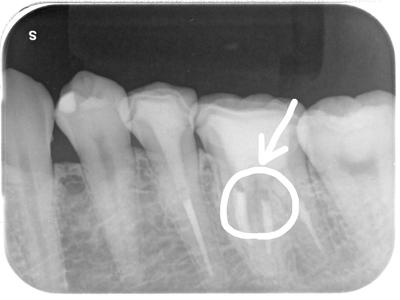

左下6部痛み。

転勤でメインテナンスが数年中断されたのだが、その時に6部レジンの欠けにより痛みが出たので、転勤先で歯科医院を受診され、抜髄、補綴治療行われたのだが、終了時より違和感が続き、とうとう痛みまででてきたため当院に相談があった。

髄床底〜近心根周囲に影があるが・・・・・結局パーフォレーションが起きていた。

イレギュラーな位置に根管口があったため、多分、前医が起こしたのだと思う。